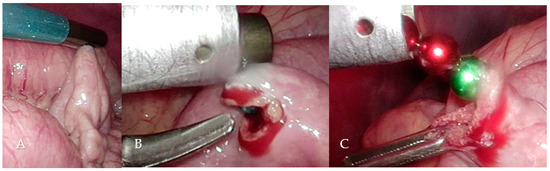

During laparoscopy in routine technique (Video S2) with the patient in the French position and with a transumbilical minilaparotomy for a 10 mm trocar and two 5 mm trocars in the right and left lower quadrant, the all-round view showed normal upper and lower abdominal organs. Through the 10 mm trocar, a magnetic rod (Figure 5) was inserted intra-abdominally, and the entire small intestine was scanned starting from Bauhin’s valve.

The magnets could be localized in the mid-small bowel region during this procedure just after a few minutes (Figure 6A). A laparoscopic enterotomy was performed, and the 7 magnets were attracted and fixed by the magnetic rod and extracted directly through the trocar (Figure 6B,C). The enterotomy was closed with three Vicryl 4-0 sutures.

Figure 6. Magnetically adherent small bowel loop (A), enterotomy with visible blue magnetic ball (B), removal of the magnetic balls (C) (see also Video S2).